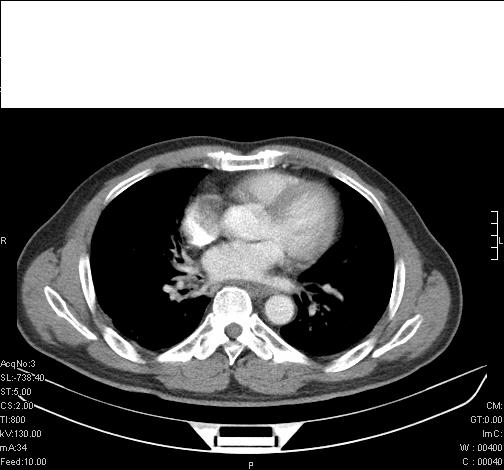

前几天,发了患者的平扫片,患者抗炎一周后增强扫描。右中叶病灶吸收明显,但下叶病灶未见明显吸收。右肺门可见结节影,看来凶多吉少

右肺下叶支气管管腔狭窄,管壁增厚,右下肺见斑片状高密度影,考虑右侧肺门中心肺癌伴阻塞性肺炎

右肺下叶支气管壁明显增厚,考虑癌症并阻塞性炎症、肺门淋巴结肿大

考虑右肺癌并阻塞性炎症、肺门淋巴结肿大

右肺下叶支气管壁不规则增厚,右肺下叶有斑片状影分布。考虑右肺中央型肺癌伴右肺下叶阻塞性改变。建议支纤镜检查。平扫比增强较好显示了病变情况。

右主支气管狭窄,管壁增厚。考虑右中心性肺ca伴阻塞性肺炎。

既然抗炎治疗有效,可继续治疗;右肺下叶支气管管腔狭窄,管壁增厚,右下肺见斑片状高密度影,右侧主支气管后见结节影(淋巴结?),肺癌不能排出。